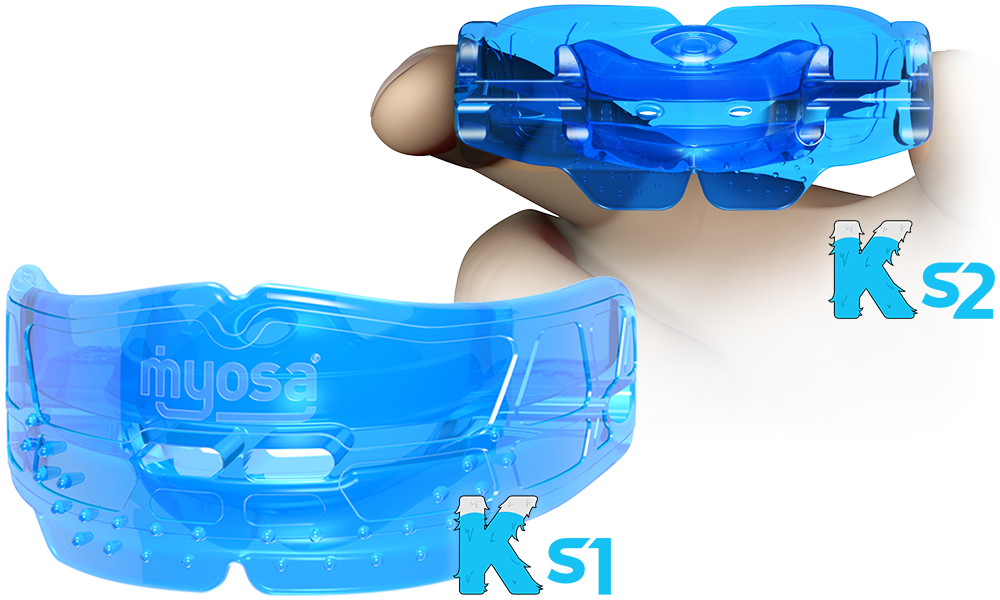

EARLY INTERVENTION

Early Orthodontic Solutions: RME and Myobrace Appliances Modern orthodontic treatment offers a range of tools designed to guide healthy dental development in children. Two key appliances—Rapid Maxillary Expansion (RME) and Myobrace—play vital roles in early orthodontic care by addressing jaw development and oral habits. Here’s a look at what each does and how they help… Read.

Ella C. – RME + Myobrace – Mixed Dentition, Class II Div 1 with Moderate to Severe Crowding